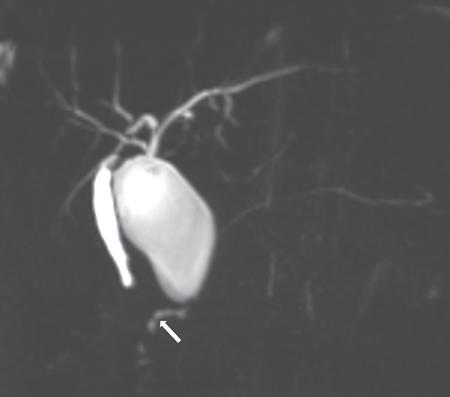

Priscilla Joshi, Mangal Subhash Mahajan, Vandana Jahanvi Imaging is important in paediatric patients with pancreatic pathologies which can be congenital, pancreatitis or neoplastic. Congenital pancreatic anomalies predispose the children to recurrent attacks of pancreatitis and other complications. Paediatric pancreatic tumours are uncommon but when they do occur imaging is essential for their diagnosis, staging and posttreatment follow-up. Pancreas divisum is the most common congenital pancreatic anomaly. It occurs in approximately 4%–14% of population. Failure of fusion of dorsal and ventral pancreatic ducts results in pancreatic divisum. Three variants of pancreatic divisum are known: In most cases, pancreatic divisum is asymptomatic. However, it may give rise to recurrent episodes of pancreatitis. Pancreatitis is believed to occur due to inadequate drainage of pancreatic secretions by the duct of Santorini. Pancreatic divisum is easily identified on MRCP (magnetic resonance cholangiopancreatography) which is a noninvasive technique and therefore is now increasingly being performed over ERCP to avoid ERCP-induce pancreatitis. Secretin-induced MRCP improves the visualization of the pancreatic ducts. The dorsal duct can be seen passing the CBD anteriorly and superiorly on imaging. This entity can also be identified on MDCT if the pancreatic duct is visualized. Rarely, it may be associated with cystic dilatation of terminal portion of duct of Santorini which is called Santorinocele. Failure of rotation of ventral bud along with the duodenum results in encasement of duodenum by a rim of pancreatic tissue and this entity is known as annular pancreas. The band of pancreatic tissue encircling the duodenum could either completely or partially surround the duodenum and is in continuity with pancreatic head. It occurs in approximately 1 in 20,000 population. Not all cases of annular pancreas present in childhood. In paediatric age group, it can present as neonatal duodenal obstruction because of associated duodenal stenosis. Children and adults with annular pancreas may also present with recurrent pancreatitis, postbulbar duodenal ulcerations or biliary obstruction. On upper gastrointestinal studies (barium meal), characteristic narrowing of second part of duodenum is seen. CT and MRI may show rim of pancreatic tissue encircling the duodenum. In partial annular pancreas (Fig. 9.16.2), pancreatic tissue is seen extending posterolateral or anterolateral to the duodenum with the pancreatic tissue giving a ‘crocodile – jaw’ configuration. This in the presence of gastric outlet obstruction helps in the diagnosis of incomplete annular pancreas. MRCP shows the pancreatic duct encircling the second part of the duodenum and entering it over its right lateral aspect. The pancreatic duct draining the annular segment usually drains into the main pancreatic duct. It can also drain into the intrapancreatic portion of common bile duct, the duct of Wirsung or the duct of Santorini. Secretin-induced MRCP because of its ability to demonstrate ductal anatomy well may become the best noninvasive imaging modality for diagnosis of pancreatic ductal variants including annular pancreas. Other causes of paediatric duodenal obstruction should be kept in mind while diagnosing annular pancreas. Other than annular pancreas, the presence of duodenal narrowing on barium study in neonates, should raise the possibilities of duodenal atresia, duodenal web and Ladd’s bands. In duodenal atresia, the contrast does not pass beyond the obstruction and no air is seen on radiograph beyond the atretic segment. Whereas, in annular pancreas, intestinal gas is seen distal to the involved segment. And on upper gastrointestinal studies, the duodenal bulb is distended with slow transit of oral contrast through the stenosed duodenal segment distally. In duodenal web classical ‘wind–sock’ diverticulum is seen due to distal stretching of the web forming an intraluminal pseudodiverticulum. On barium studies, thin radiolucent membrane is seen due to filling of barium within the lumen and around the diaphragm. The mutation in the developmental protein IPF1, results in pancreatic agenesis. It is very uncommon as it is incompatible with life. Anomalies associated with this condition are: foetal growth restriction, agenesis of gallbladder and polysplenia. Hypoplasia or partial agenesis occurs due to nondevelopment of dorsal or ventral pancreatic bud. Partial agenesis of the dorsal pancreas is more common than agenesis of the ventral portion. However, complete dorsal pancreatic agenesis is rare. Dorsal pancreatic agenesis is often associated with heterotaxia syndrome. Partial dorsal pancreatic agenesis is more common than partial ventral agenesis. Complete dorsal pancreatic agenesis is however rare. In partial dorsal agenesis, short rounded head of pancreas is seen adjacent to the duodenum with absence of pancreatic neck, body and tail; however, remnant of duct of Santorini and minor duodenal papilla are generally present. In complete dorsal agenesis, both the minor duodenal papilla and the duct of Santorini are absent. The distal pancreas contains the islet cells, hence those with dorsal agenesis are at a higher risk of developing Diabetes Mellitus. This uncommon condition is diagnosed when there is an accessory lobe of pancreatic parenchyma originating from the main gland and draining through an aberrant duct. The accessory lobe may be of varying size and may drain into the main pancreatic duct through a narrow or a wide communication. Association with gastric duplication cyst is known and if present the aberrant duct communicates with the gastric duplication cyst and the main pancreatic duct. Accessory pancreatic lobe may present as acute pancreatitis which is believed to result from obstruction of the pancreatic duct by viscus secretions, ulcer bleeding or biliary sludge. Ectopic pancreatic tissue can be seen in 0.6%–13.7% of population. It is most commonly seen in the stomach or duodenum. The ectopic tissue is generally located in the submucosa. Although, usually asymptomatic, it presents as stenosis, ulceration, gastrointestinal haemorrhage or intussusception. Pancreaticobiliary maljunction is a congenital abnormality in which the main pancreatic and common bile ducts join outside the duodenal wall that forms a common channel. It was first described by Arnolds in 1906. Women are more frequently affected than men with a female to male ratio of 3:1. It is predominantly present in young women. Its incidence is 0.9%–6.2% on ERCP and 61.8%–70% on autopsy. Although few familial cases have been reported whether pancreaticobiliary maljunction is hereditary remains unclear. It is diagnosed on the basis of radiological findings or anatomical findings at surgery or autopsy. Hence, radiologist play crucial role in making diagnosis of this entity. Pathogenesis of pancreaticobiliary maljunction is controversial. Several studies have proposed that anomalous development of the ventral pancreas with abnormal fusion between the bile duct and branches of the ventral pancreatic duct is responsible for development of pancreaticobiliary maljunction. Normally, the main pancreatic duct and common bile duct open either separately or join to form a common channel that opens in second part of duodenum. Length of the common channel varies between 1 and 12 mm normally. Sphincter of Oddi is present at the distal end of pancreatic and common bile ducts. It regulates outflow of pancreatic and bile juice. The sphincteric control at the pancreaticobiliary junction is important for the regulated drainage of bile and pancreatic juice. In maljunction, as the union of the bile duct and the pancreatic duct is outside the duodenal wall, the sphincter of Oddi is unable to regulate the flow of pancreaticobiliary juices resulting in bidirectional regurgitation of juices (Graphic 9.16.1). It produces various pathological conditions in the biliary tree and pancreas. On the basis of dilatation of common bile duct, pancreaticobiliary maljunction is divided into that with biliary dilation and without biliary dilatation. The former is more common and present in 77% of cases. The latter is less common and present in remaining 23% of cases. New Komi classification (Graphic 9.16.2) is based on how the pancreatic and common bile ducts join. It takes into account presence or absence of the common channel dilatation and the concept of pancreatic divisum. Type I union is bile duct type, in which the common bile duct joins the pancreatic duct at right angle. It has single papilla. It is subclassified into type IA and IB based on absence or presence of the common channel dilatation respectively. Type II union is pancreatic duct type, in which the pancreatic duct joins the common bile duct at an acute angle. It also has single papilla. It is subclassified into type IIA and IIB based on absence or presence of the common channel dilatation, respectively. Type III is complex type, in which the two ducts join in complex configuration. It has two papillae. It is subclassified into type IIIA, IIIB and IIIC. Type IIIA is similar to pancreatic divisum with biliary dilatation. Type IIIB is characterized by absence of duct of Wirsung. Type IIIC is further subclassified into IIIC1, IIIC2 and IIIC3. A thin communicating duct between the main and accessary ducts is present in type IIIC1. A common channel is made up of common and accessary ducts of equal calibre in type IIIC2. There is complex network of enlarged ducts that join each other by total or partial dilatation of the ductal system in type IIIC3. Japanese Study Group on Pancreaticobiliary Maljunction proposed a new classification (Graphic 9.16.3) in 2015 on the basis of formation of pancreaticobiliary maljunction. According to this new classification, pancreaticobiliary maljunction is divided into four types: (1) Stenotic type: The common channel is joined by the distal CBD with stenosis, (2) Nonstenotic type: The common channel is joined by the distal CBD without stenosis, (3) Dilated common channel type: As the name suggests, the common channel is dilated and (4) Complex type: A complicated pattern is formed by the pancreaticobiliary junction. Pancreaticobiliary maljunction with congenital biliary dilatation have higher incidence of symptoms in neonatal and infantile period and manifest as jaundice and abdominal mass. Less common symptoms include abdominal pain, vomiting and fever. Dilatation of common bile duct is an important finding on ultrasonography and further imaging with magnetic cholangiopancreatography is recommended to look for the status of common channel. Pancreaticobiliary maljunction without congenital biliary dilatation is more difficult to diagnose because of less frequent symptoms and less remarkable imaging findings. These patients are frequently asymptomatic but may presents as abdominal pain and hyperamylasaemia in adulthood. Many adult patients may show signs of biliary cancers. Focal or diffuse gallbladder wall thickening may be an early clue for the diagnosis. Hence, pancreaticobiliary anatomy should be assessed by magnetic resonance cholangiopancreatography when no specific cause of gallbladder wall thickening is established. The diagnosis of pancreaticobiliary maljunction is made when there is an abnormally long common channel of the pancreatic duct and the CBD; or there is an abnormal union between the pancreatic and bile ducts seen on an investigation which directly images these structures. These include endoscopic retrograde cholangiopancreatography, percutaneous transhepatic cholangiography or intraoperative cholangiography, magnetic resonance cholangiopancreatography or three-dimensional drip infusion cholangiography computed tomography (CT). However, when the common channel is relatively short, it is crucial to confirm that the effect of the papillary sphincter does not extend to the junction with direct cholangiography. There is no clear definition of a long common channel. Few authors suggest 8 mm or longer while others suggest 15 mm or longer as a long common channel. It can also be diagnosed if the pancreaticobiliary junction is demonstrated outside the duodenal wall on endoscopic ultrasound or multiplanner reconstruction images of multidetector-row CT. Pancreaticobiliary junction must be present outside the duodenal wall or the union of pancreatic or bile duct must be abnormal at surgery. Elevated amylase levels in the bile within the bile duct and gallbladder obtained immediately after laparotomy and presence of extrahepatic biliary dilatation strongly suggest the existence of pancreaticobiliary maljunction. Rarely, the amylase levels are close to or below the normal serum value in these patients. When cystic, fusiform, or cylindrical dilation is present in the extrahepatic bile ducts, detail workup is necessary to determine whether pancreaticobiliary maljunction is present. To diagnose biliary dilatation, maximum calibre of the common bile duct is measured. Diagnosis of bile duct dilatation is age-dependent (Table 9.16.4). Ultrasound is used as screening tool and alone may not be enough to detect an anomalous pancreaticobiliary junction. Extrahepatic bile duct dilation or gallbladder wall thickening are the clues to make early diagnosis of pancreaticobiliary junction. Endoscopic ultrasound demonstrates the pancreatic and bile duct junction outside the duodenal wall and help to diagnose pancreaticobiliary maljunction. Magnetic resonance cholangiopancreatography is an accepted noninvasive imaging tool to demonstrate the pancreaticobiliary anatomy. It is preferred over ERCP. Source images and maximum intensity projection images of 3D MRCP are very useful to delineate the pancreaticobiliary anatomy. Its sensitivity is 75% in adult and 44%–65% in children. Fig. 9.16.3 shows a case of Pancreaticobiliary maljunction with Choledochal cyst. Secretin-stimulated dynamic MRCP and time-spatial labelling inversion pulse (Time-SLIP) can be used to identify the pancreaticobiliary reflux. Secretin stimulates the exocrine pancreas to secrete fluid. This increase of fluid content within the lumen of pancreatic duct improves visualization. In pancreaticobiliary maljunction, there is enlargement and retrograde increase in signal intensity of the common bile duct. Time-SLIP MRI allows direct visualization of pancreaticobiliary flow by placing the inversion pulse at the head and body of pancreas and suppressing the background. Gadoxetic acid-enhanced MRI is used to identify biliopancreatic reflux. Gadoxetic acid is a hepatobiliary specific contrast agent. It is taken up by hepatocytes and excreted into the bile. In pancreaticobiliary maljunction, there is retrograde increase in signal intensity of the pancreatic duct. Multiplanar reconstruction images of the contrast-enhanced high-resolution multidetector CT scan can demonstrate the communication of the pancreatic and bile ducts and help to diagnose pancreaticobiliary maljunction. Its sensitivity is 58%–100% in adults and 20% in children. Drip infusion CT cholangiography involves intravenous injection of biliary contrast agent. It demonstrates details of pancreaticobiliary anatomy; however, it sometimes fails to demonstrate the pancreatic duct preventing the diagnosis of pancreaticobiliary anatomy. Endoscopic retrograde cholangiopancreatography confirms lack of effect of the sphincter of Oddi on the pancreatic and bile duct junction. Its sensitivity is 75%. Main advantage of ERCP is that it allows bile and tissue sampling and therapeutic procedures. In pancreaticobiliary maljunction, the Oddi sphincter fails to regulate the pancreaticobiliary junction. Normally, hydrostatic pressure within the pancreatic duct is higher than that in the bile duct. Hence pancreatic juice often refluxes into the bile duct. There is increased pressure in the bile and pancreatic duct secondary to obstruction of the common channel or primary stricture of distal bile duct. Obstruction or stricture is caused by impaction from a protein plug. It is often a temporary process because these protein plugs are fragile and resolve spontaneously. It causes transient and intermittent symptoms like abdominal pain, vomiting, and jaundice. Protein plugs consist of lithostathine. It is a soluble protein secreted by pancreas. They are often depicted at ERCP but not at CT or MRCP. Incidence of acute pancreatitis in pancreaticobiliary maljunction is 30% in children and 9% in adults. Chronic pancreatitis is present in 3% of these patients. In majority, the changes are less severe but can be recurrent. Protein plugs are believed to be one cause of acute pancreatitis. Pancreatic calcifications are usually absent in chronic pancreatitis with pancreaticobiliary maljunction. Common bile duct and gallbladder calculi occur more often in adults than in children. Its incidence is 23% in adults and 9% in children. Calculi formation appears to be related to bile stasis because pigmented calculi are more commonly detected than cholesterol calculi in patients with pancreaticobiliary maljunction.

Imaging findings (Fig. 9.16.1)